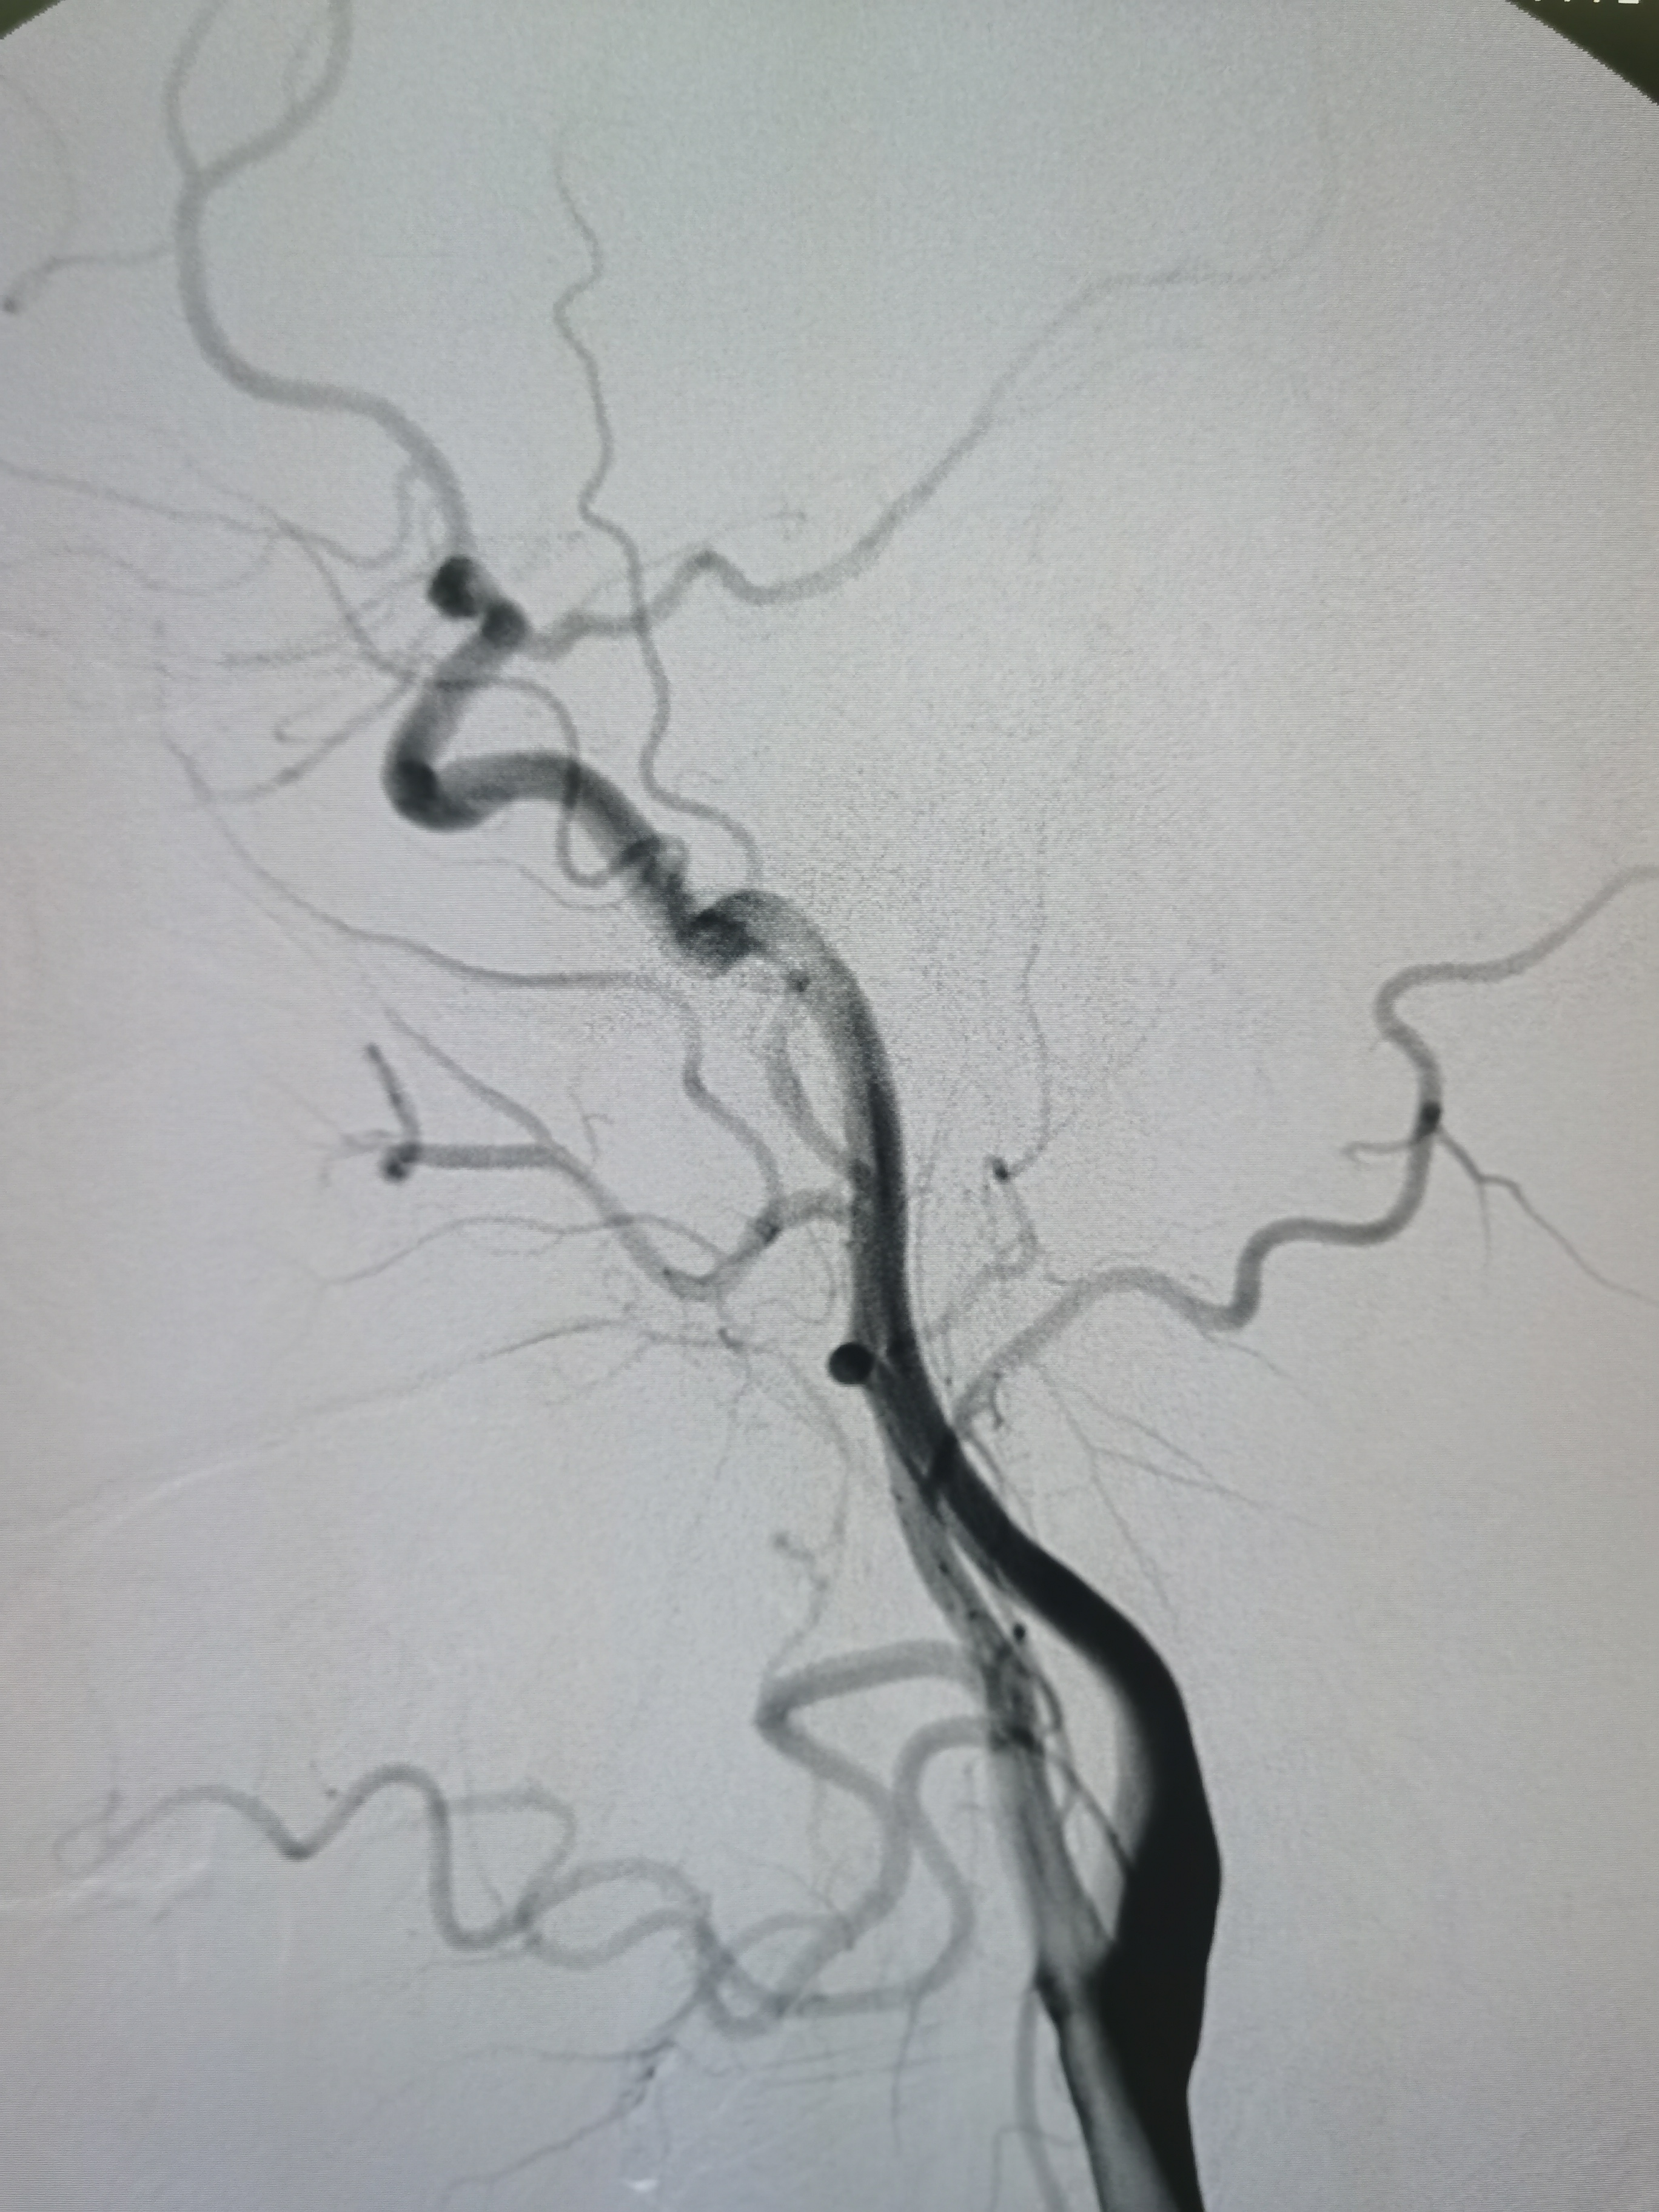

右侧颈内动脉正常。

右侧颈内动脉颅内段正常,胚胎型大脑后动脉。